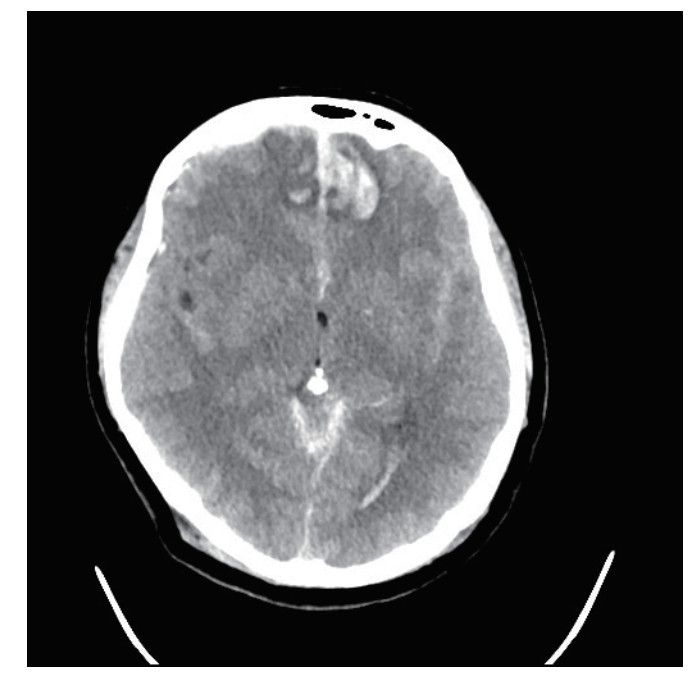

1 病例资料患者,女性,40岁,因“车祸致全身多处外伤半小时余”于2025年6月27日由120送入黄山市人民医院急诊。患者2 h前骑电瓶车发生车祸,致头面部、胸部及左下肢严重受伤,当即昏迷,伴恶心呕吐。入抢救室时自主呼吸微弱,后出现室速,伴随血流动力学不稳定,GCS评分为6分(E1V1M4),双侧瞳孔不等大、对光反射迟钝,左侧直径3 mm,右侧5 mm,后枕部头皮血肿,左下肢胫腓骨区域明显肿胀畸形。医院立即实施全面评估,经紧急行电复律、利多卡因静推后恢复自主心率,予以气管插管保护气道,建立深静脉通路泵入血管活性药物维持血压、纠正酸中毒。完善CT检查:双侧脑挫伤、创伤性蛛网膜下出血、右侧额顶部硬膜下血肿,中颅底及枕骨骨折、累及枕骨大孔,左侧胫腓骨骨折及双肺坠积性改变。见图 1,2。神经外科会诊诊断为弥漫性轴索损伤,无立即手术指征,收入EICU监护稳定生命体征。

| 图 2 枕骨骨折 |